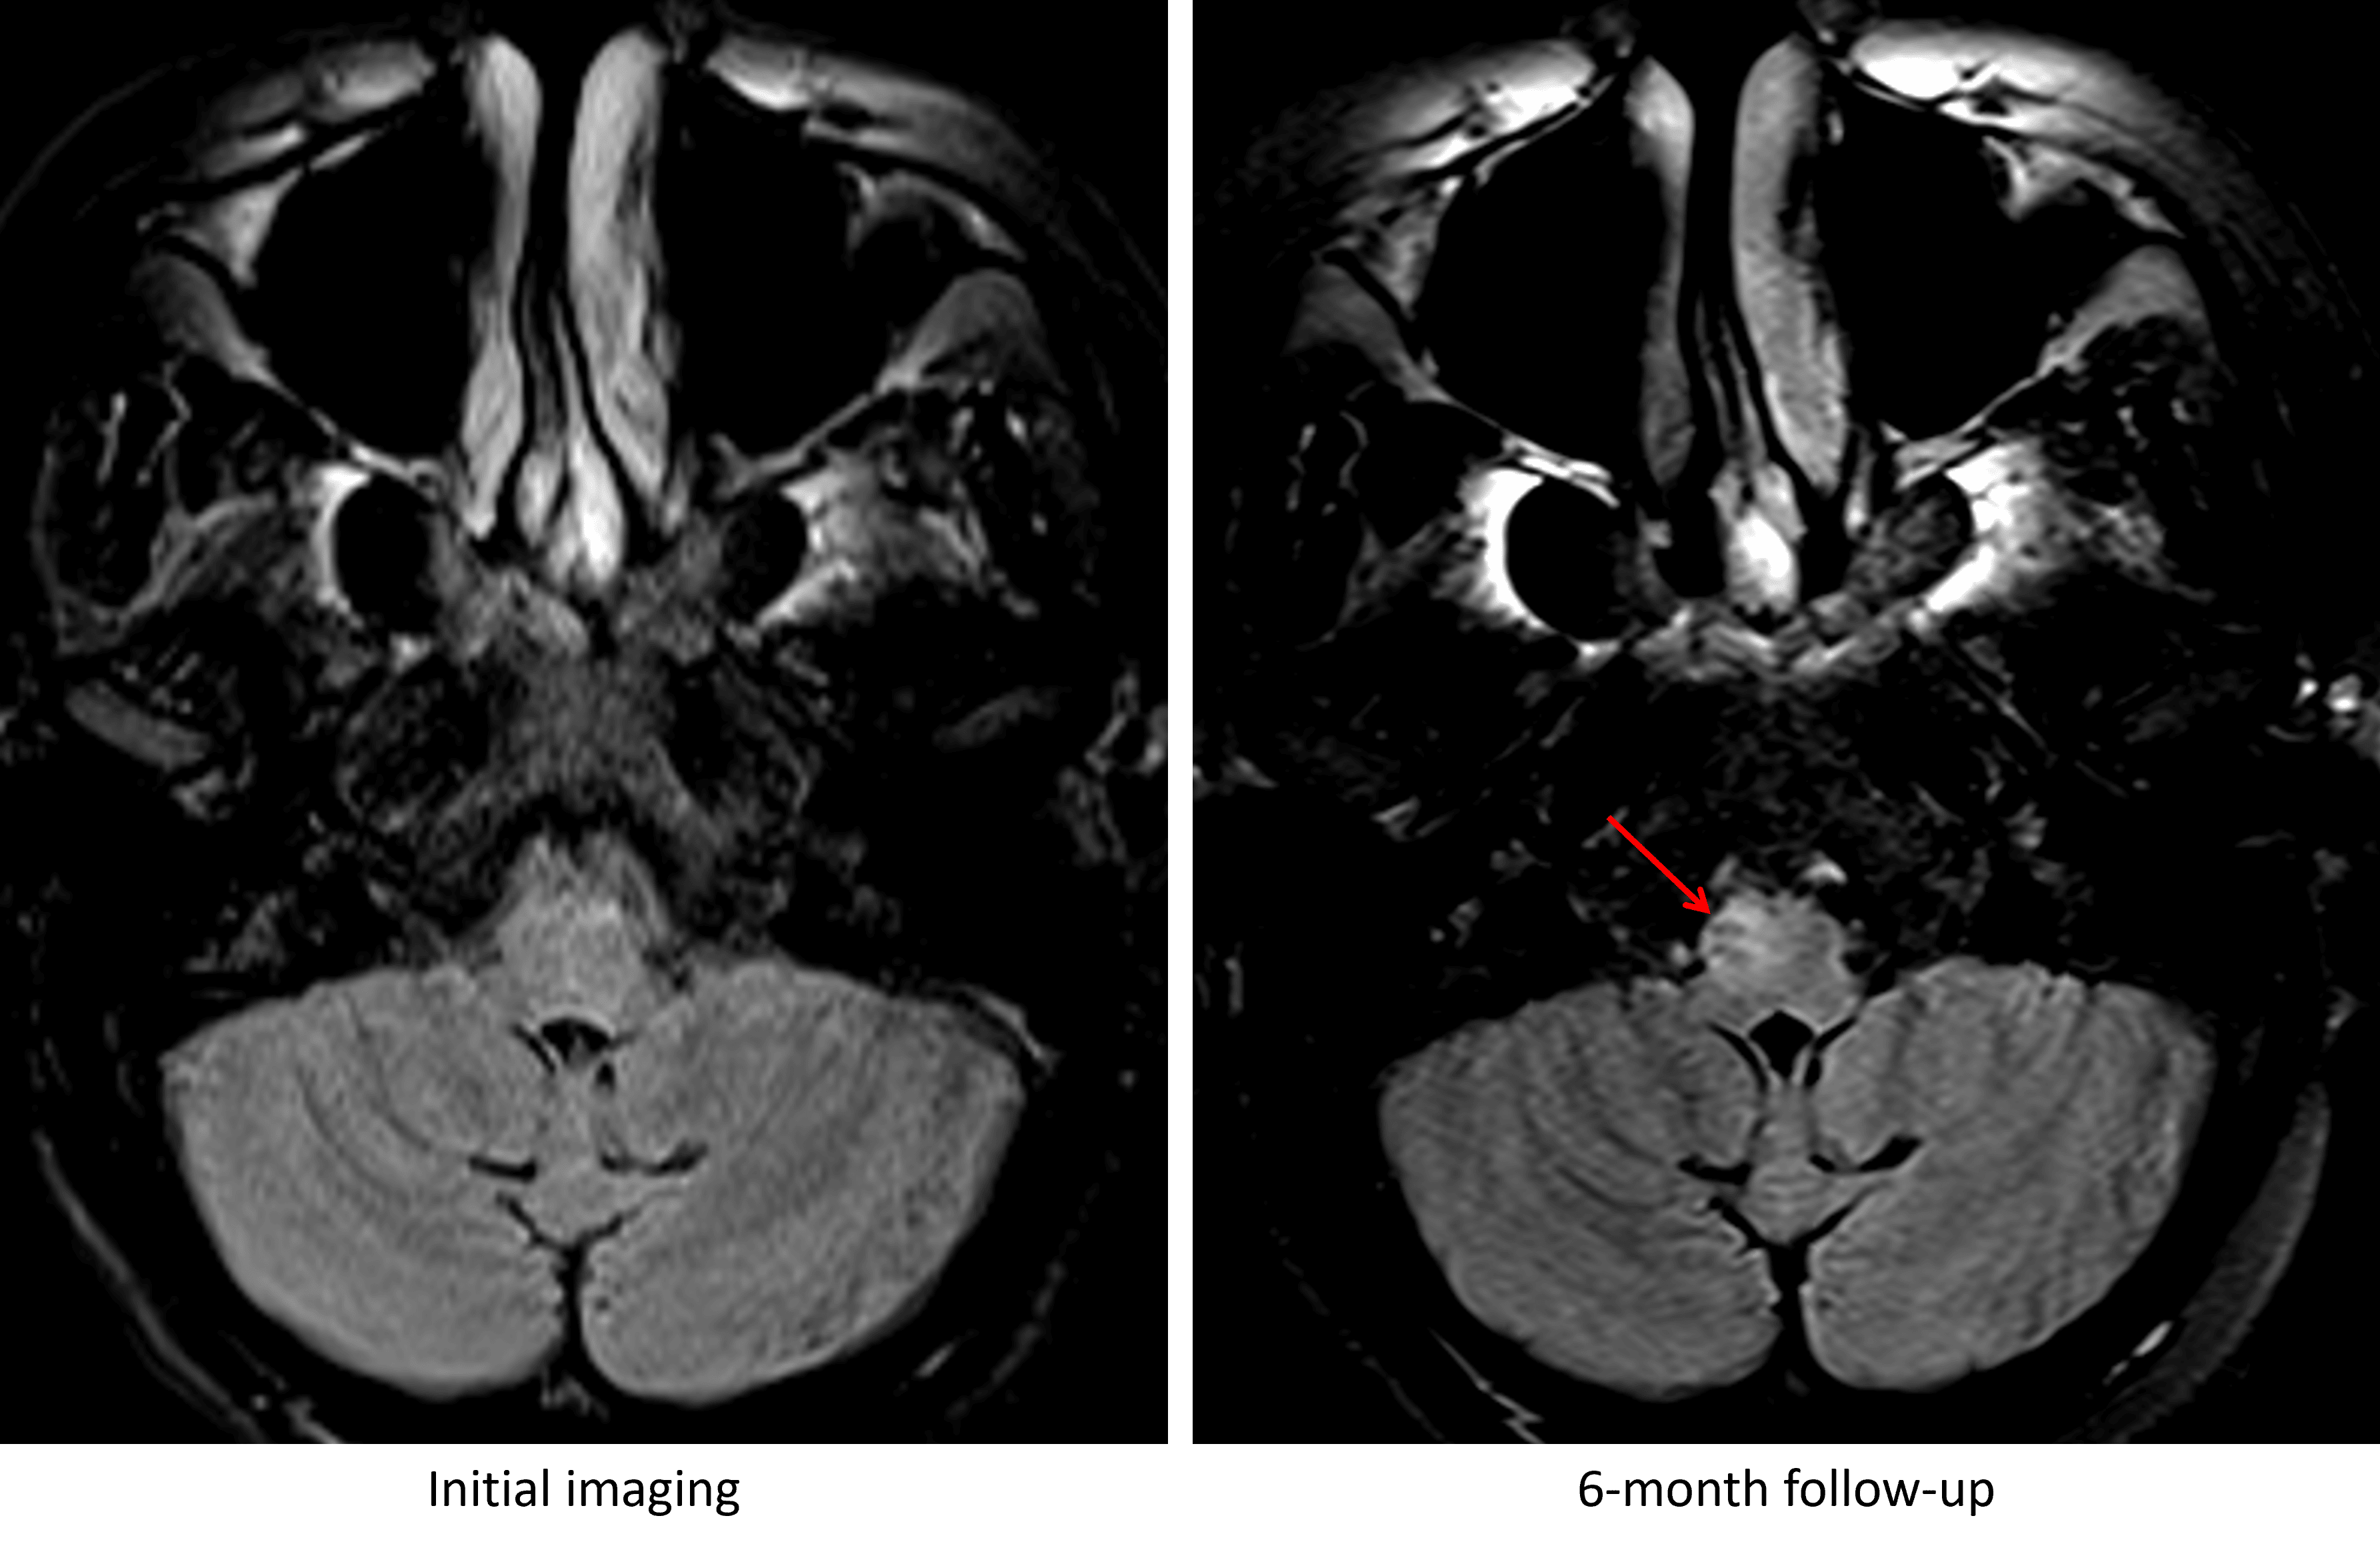

6 month follow-up MRI

- Overall improved appearance and extent of T2/FLAIR signal hyperintensity in the brainstem extending into the internal capsules

- New expansile T2 signal hyperintensity in the right ventral medulla

- No corresponding enhancement, restricted diffusion, or susceptibility artifact

Development of T2/FLAIR signal hyperintensity and enlargement of the right inferior olivary nucleus at 6 month followup imaging (red arrow).